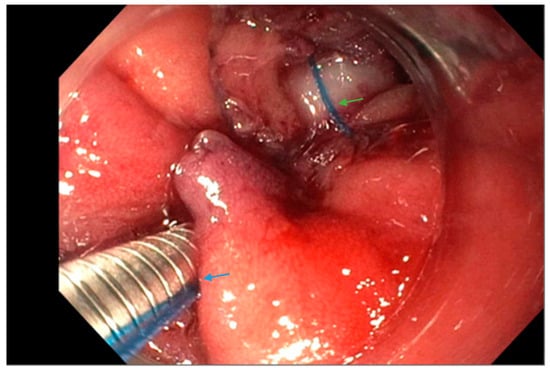

Figure 2.

Upper endoscopy reveals the use of a suturing system (arrow, blue) with a suture in place (arrow, green) at the leak site in a patient following sleeve gastrectomy.